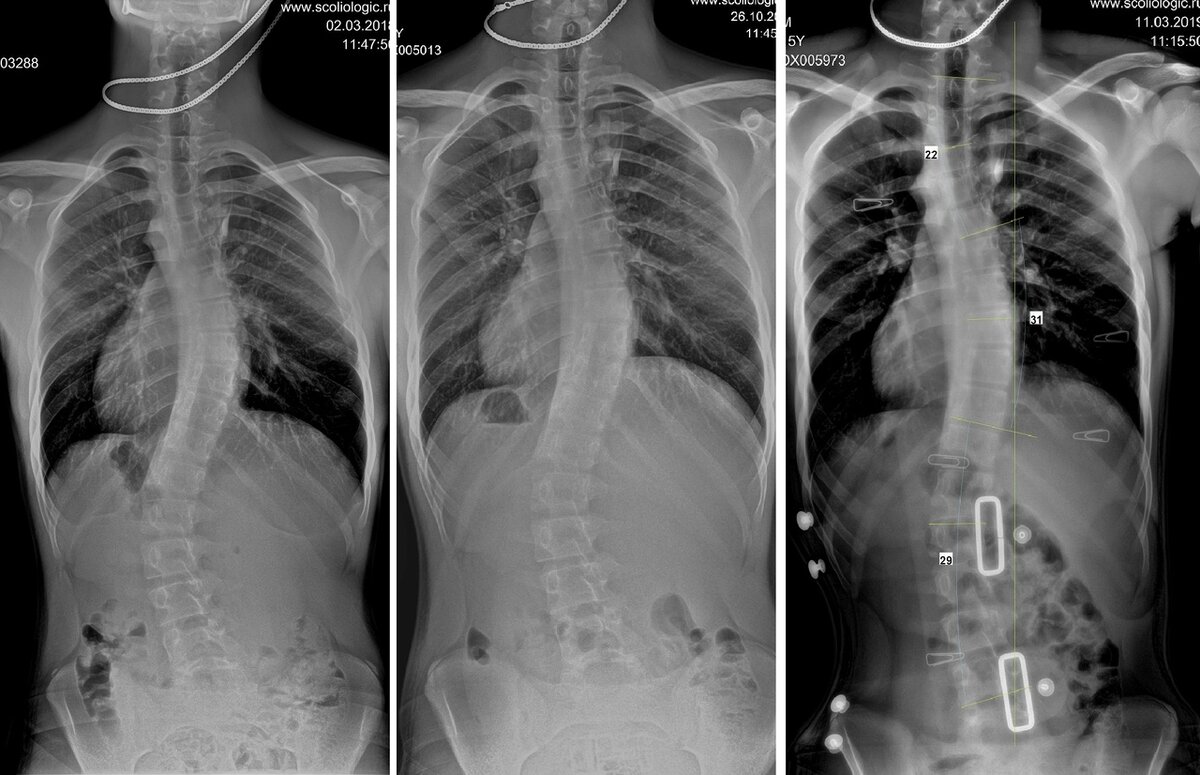

Пациент попал в Сколиолоджик.ру в марте 2018 года в 14 лет - родители предприняли последнюю попытку избежать операцию, которую уже назначили. Градусы - 52-51-41.

Через полгода в октябре 2018 года - 28-39-34.

Вчера на приеме после коррекции корсета градусы в корсете были 22-31-29.